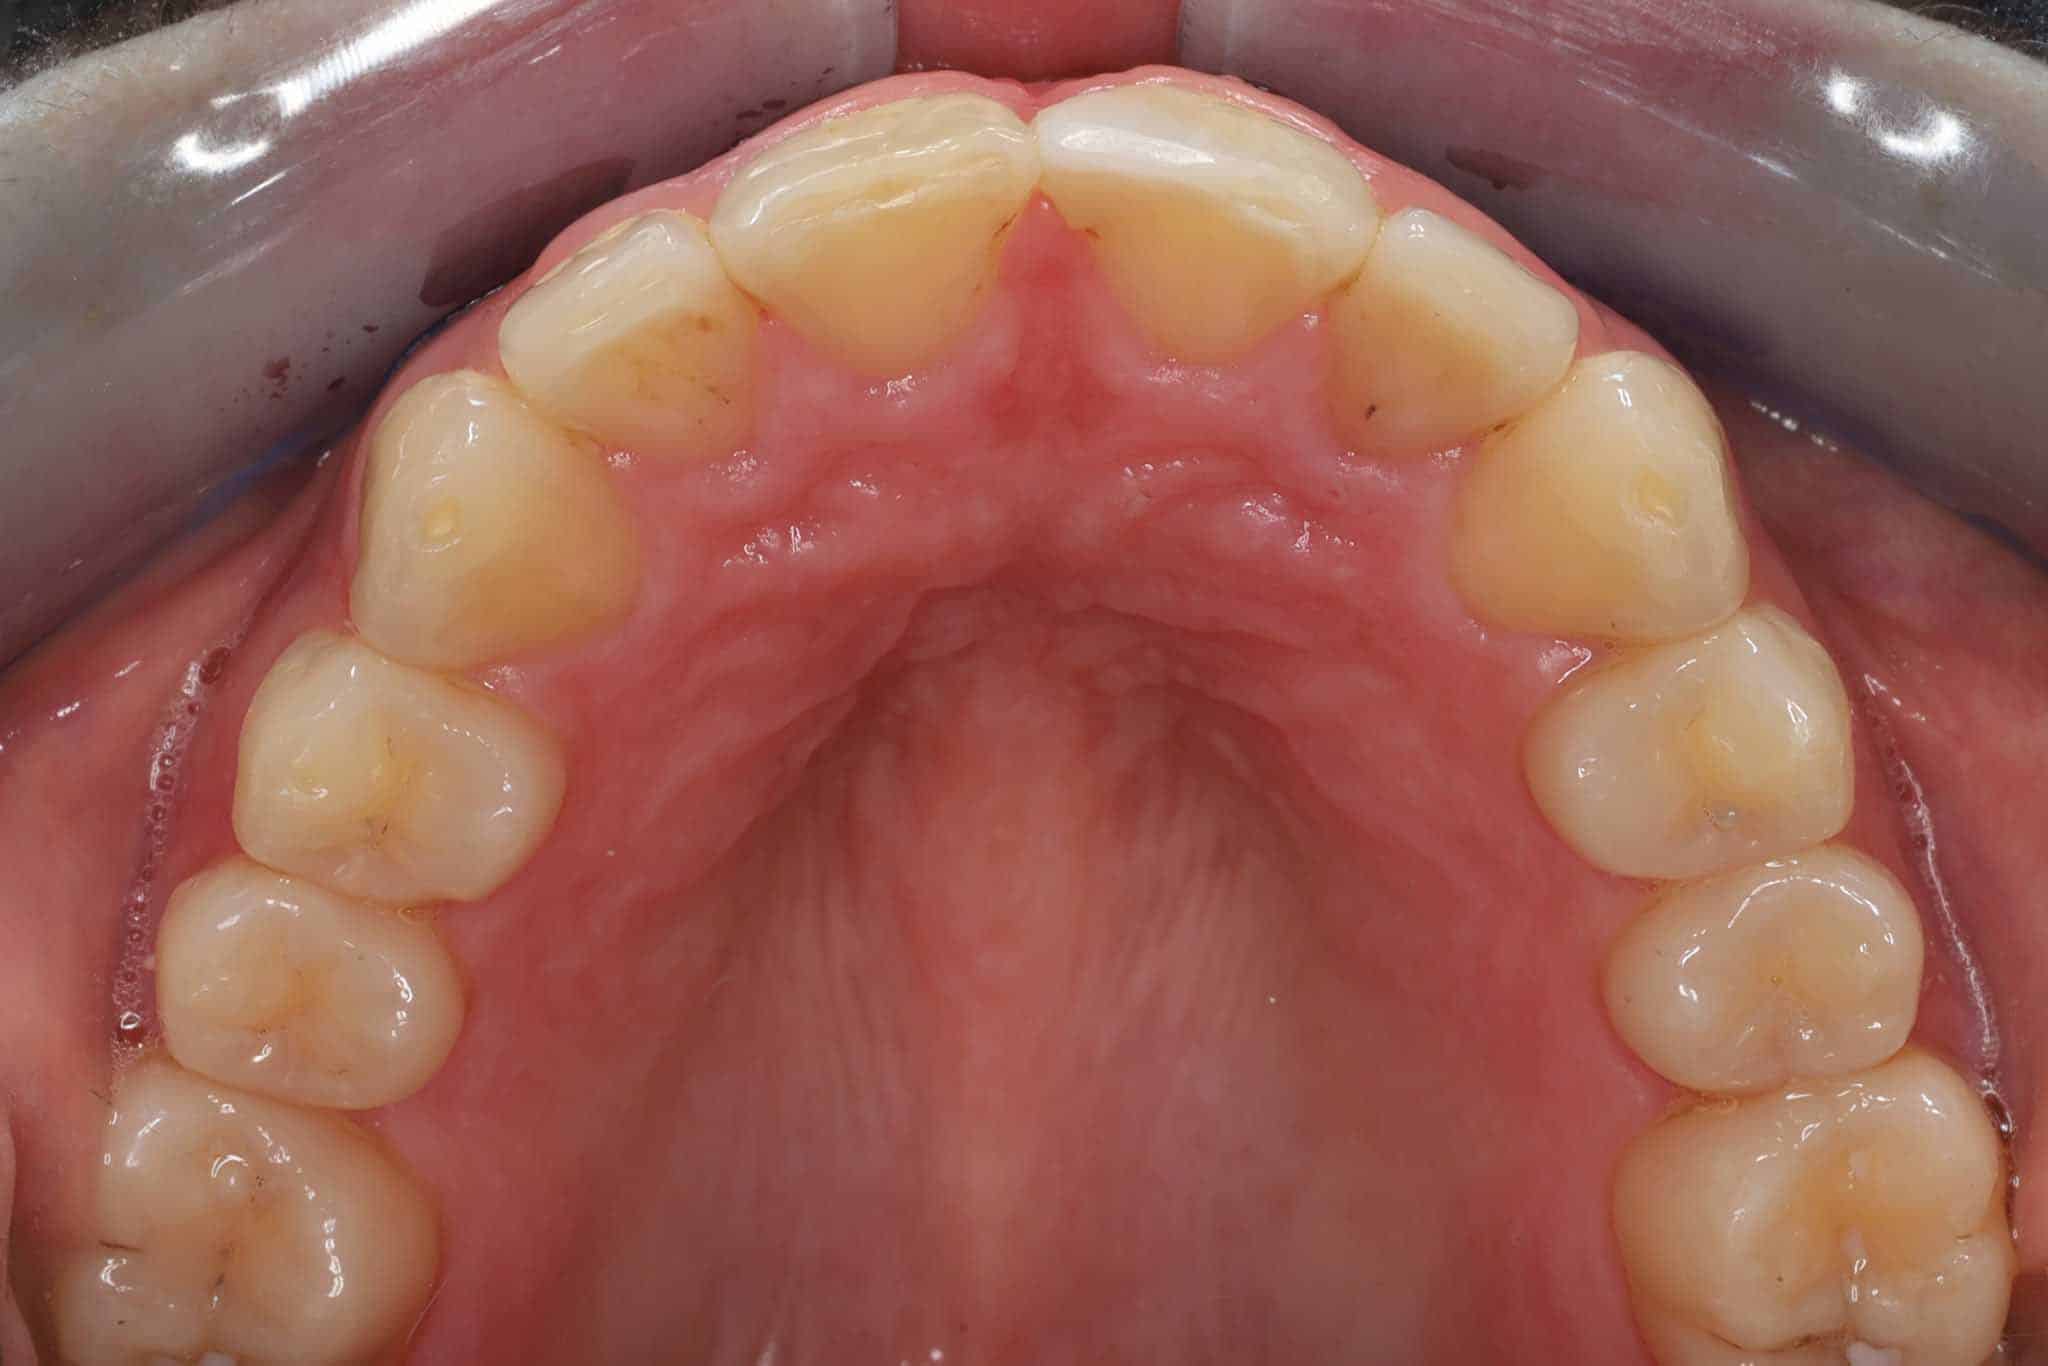

Før- og etterbilder – Resultater fra retainerbehandling

Flere bilder